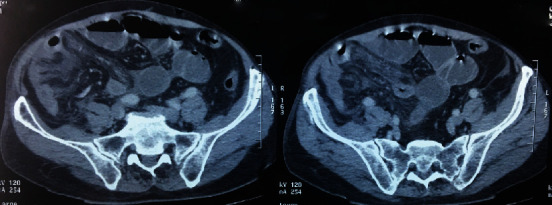

Sclerosing encapsulating peritonitis (SEP) is an unusual fibroinflammatory disease of the peritoneum marked by the development of a fibrous membrane enveloping generally the small intestines. The knowledge around this subject is not completely understood. And the etiology can be either idiopathic or secondary to several diseases, treatments, and/or medications. We present a case of a 52-year-old man suffering from atypical clinical symptoms including recurrent abdominal ascites and intestinal obstruction. An abdominal computed tomography showed findings typical of SEP. Therefore, the patient benefited from exploratory laparotomy, which confirmed the diagnosis of idiopathic SEP. Postoperatively, he again had an episode of bowel obstruction, but this was controlled with steroids. Diagnosis of SEP is a real challenge to surgeons, gastroenterologists, and radiologists. And imagery is very helpful to make the diagnosis. Consequently, it is imperative that all hospital practitioners should distinguish between this lesion and other etiology of acute peritonitis.

Abstract Image